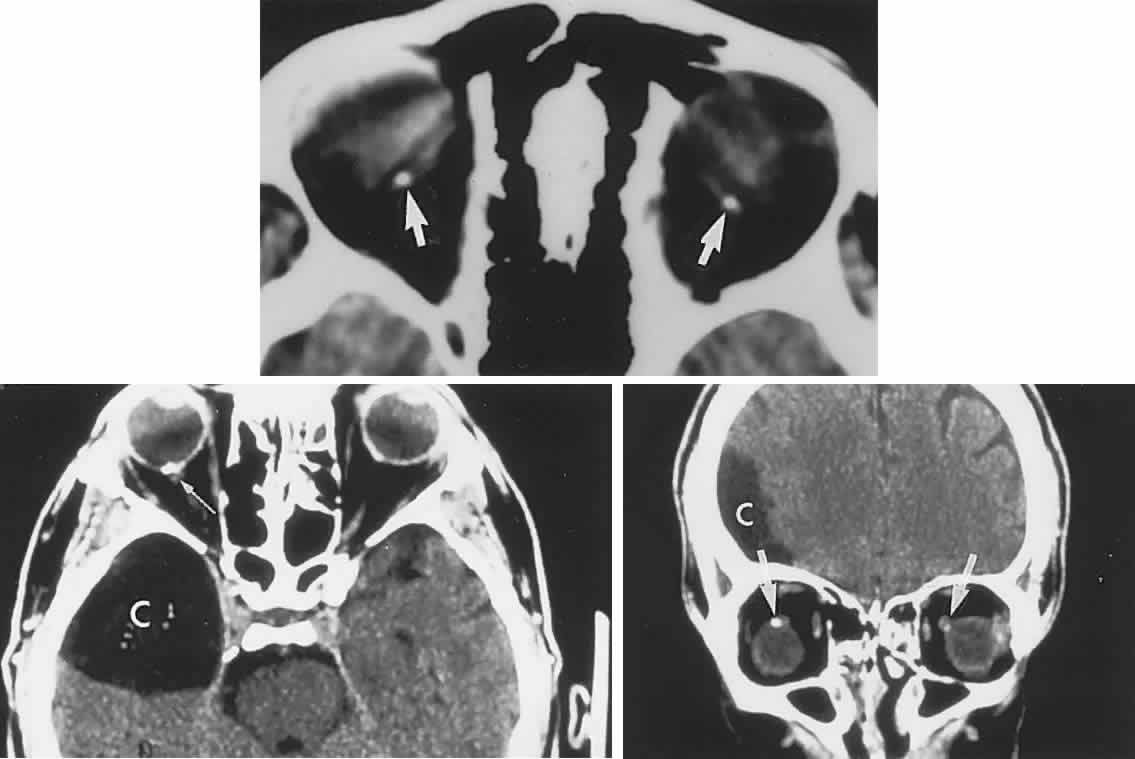

Biochemical assays have considerably clarified the nosologic status of the group of storage diseases previously classified as the “cerebromacular degenerations,” of which Tay-Sachs disease is the eponymous prototype. Although these disorders share a superficial resemblance, showing a progressive neurodegenerative course with variable fundus findings, they are now best classified by abnormal storage products (e.g., sphingolipidoses, mucopolysaccharidoses, and mucolipidoses) and lysosomal enzyme deficiencies. Lysosomes contain hydrolytic enzymes that degrade proteins, polysaccharides, and nucleic acids; if undegraded, these materials accumulate in lysosomes and impair cell function. The complex lipids and saccharides indigenous to neural cells produce symptoms and signs related to eye and brain, including corneal clouding, macular “cherry-red spot,” pigment epithelial degenerations, optic atrophy, mental deterioration, seizures, motor incoordination, myoclonus, and death.

The ganglion cell layer of the retina is a principal site of abnormal accumulation of anomalous storage products, such that ophthalmoscopic changes are observable either in the form of retinal “graying” or the well-known cherry-red spot. The ganglion cell layer densely surrounds the thin fovea, which transmits the normal red color of underlying choroid (Fig. 4). The storage disorders with cherry-red spot or macular graying are listed in Table 2.27

Fig. 4. “Cherry-red spot” of advanced Tay-Sachs disease (gangliosidosis). Note the central foveal window surrounded by a ring of densely opaque retinal ganglion cell layer; also, optic atrophy.